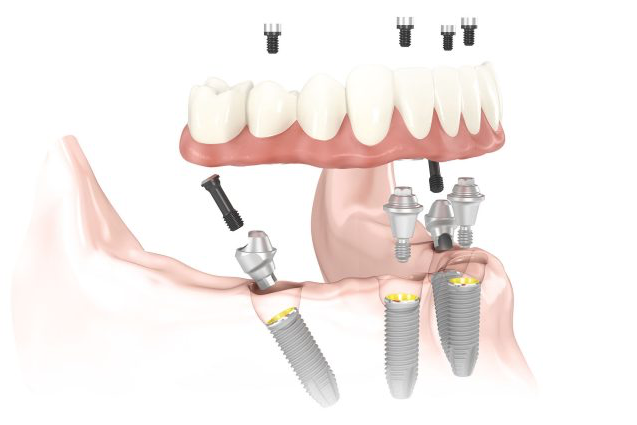

Il carico immediato consente di intervenire per un singolo elemento, per più elementi distinti e per intere arcate complete. Per una intera arcata sono sufficienti da quattro a sei impianti per riabilitare completamente la funzione estetica e masticatoria a seconda che si tratti di mandibola o di mascellare superiore.

II fase o tempo dell'inserimento degli impianti: in questo tempo terapeutico si procede all’inserimento di impianti in titanio nelle zone edentule delle ossa mascellari e/o mandibolari. Grazie alla particolare tipologia di impianti specifici e al corretto posizionamento degli stessi, è possibile procedere direttamente con la fase protesica. L’intervento sarà completamente indolore grazie anche all’ausilio della sedazione cosciente (previa valutazione medica del nostro anestesista).

III fase, posizionamento della protesi sugli impianti: fase chirurgica: con il supporto del Laboratorio Odontotecnico Design Dentale (www.designdentale.it) e della Dottoressa Daniela Gasparini, entro poche ore saremo in grado di fissare gli elementi dentali direttamente sugli impianti inseriti durante la prima fase chirurgica. Ogni protesi è personalizzata e il risultato estetico sarà assolutamente naturale: questo è possibile anche grazie allo studio del caso preliminare effettuato pre-intervento con l’ausilio di foto ed impronte di ogni singolo paziente e tecnologia digitale CADCAM.